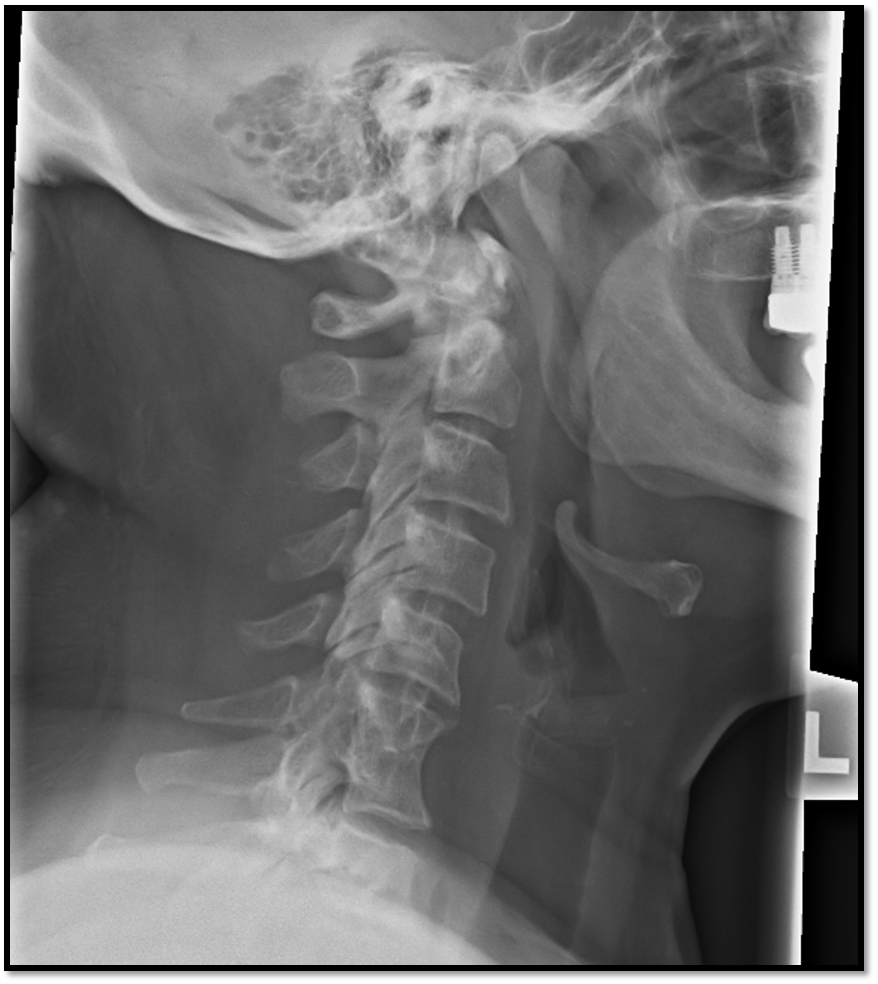

Lateral Cspine Criteria

• SI’d articular pillars and open zygopophyseal joints

• superimposition of posterior vertebral bodies

• mandible off spine

• open intervertebral spaces

A

• rotation issue: posterior borders arent aligned

• tilt issues: double lines at zygo joints

• need to do swimmers: cant see C7 and T1

• rotation and tilt issue

• swimmers not needed (fusion of C6/C7)

• chin on mandible

• rotation and tilt

• would need swimmers or more relaxed shoulders

slight rotation and tilt at the top